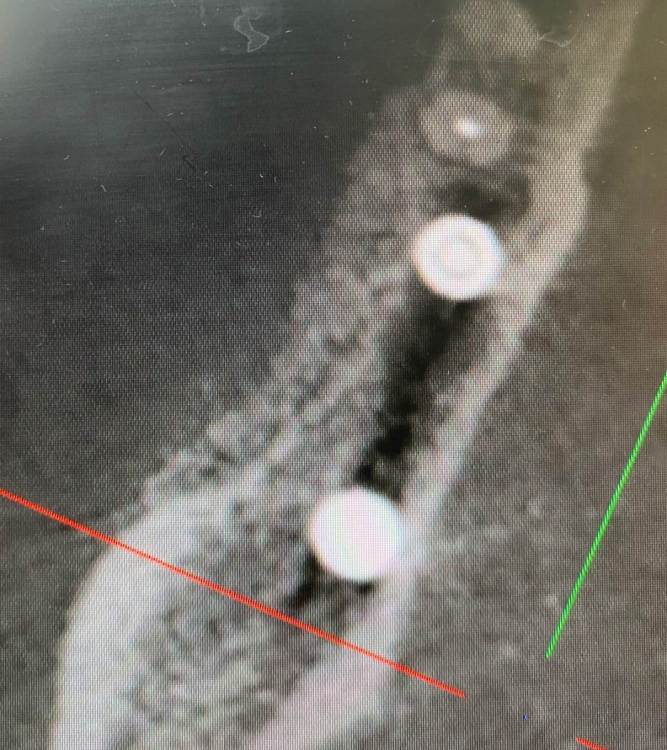

колесников Опубликовано 6 июля, 2022 Поделиться Опубликовано 6 июля, 2022 Здравствуйте коллеги! Впервые вижу перелом Астры. Впервые получил перелом «своей»Астры. Вероятно ещё никто не видел перелом Астры профайл. Диаметры 4.5 и 5.0. Самое неприятное что это произошло за 1,5 года. Ошибка протезирования. Перегруз. Резорбция. Фрактура. Из интересного. Одновременно с имплантацией была произведена контурная пластика поднадкостнично,графт шурос. Это работает. Ставим галочки и двигаемся дальше. 2 1 1 Ссылка на комментарий

колесников Опубликовано 6 июля, 2022 Автор Поделиться Опубликовано 6 июля, 2022 5 часов назад, Aquarius сказал: Спасибо за столь познавательный кейс!!! Я где- то читал, что вроде как перегруза на полностью интегрированных имплантах быть не может. Вроде как первично надо высвободить какую-то площадь импланта от кости ( воспаление, резорбция) чтобы он треснул. А не наоборот. Автор сего высказывания ссылался на то, что в связке имплант-коронка есть куда более слабые места , чем стенка интегрированного импланта. Например, фиксирующий винт. Для конического соединения это утверждение не применимо. Очень часто получаем холодную сварку имплант-абатмент,винт совершенно не работает. Протокол отработан как автомат Калашникова,платформа относительно Зенита и вершины гребня,высота уступа,наличие и ширина прикреплённой слизистой. Далее процесс запускается вспять и через два года наблюдаем прирост кости на скосе гребня. Радиальная Резорбция в виде кратера это всегда перегруз. Импланты не болят. Вокруг них нет посредника-связки,нет проприорецепции. Между тем диссонанс окклюзии со временем нарастает,тк зачастую имеются разнородные по плотности материалы в полости рта. Отчасти пациент тут виноват,не продолжил лечение,пропал на год. Но основная вина ортопеда. Причина личная. Коронка на 45 осталась от старого моста,44 вовсе пародонтитный. Желая их «спасти» вывел из прикуса,основная нагрузка справа упала на импланты. Третий сектор провисший мост 34.35-38 с подвижными 34,35 ,оставлен не тронутым. Хорошая хирургия пошла в утиль по причине малодушия. В итоге когда я стал все это разматывать и рисовать перспективы,пациент сам настоял на тотальной работе. Слабину не даём,за всеми следим. 1 Ссылка на комментарий

колесников Опубликовано 6 июля, 2022 Автор Поделиться Опубликовано 6 июля, 2022 1 минуту назад, pit сказал: Удивительная и печальная история. Диаметр 4,5 как мог сломаться??? Ладно 4.5,но 5.0! Я в публикациях такого не встречал никогда. Это к вопросу о величине жевательной нагрузки. Ссылка на комментарий

Astronaft Опубликовано 12 июля, 2022 Поделиться Опубликовано 12 июля, 2022 (изменено) 06.07.2022 в 14:28, колесников сказал: Протокол отработан как автомат Калашникова,платформа относительно Зенита и вершины гребня,высота уступа,наличие и ширина прикреплённой слизистой. Далее процесс запускается вспять и через два года наблюдаем прирост кости на скосе гребня. Это хорошай заговор-пожелание. В жизни часто не так. По одной простой причине общее здоровье человека влияет намного сильнее. Пародонтологический статус - если есть карманы хоть 5-6мм где-то во рту риск пери-имплантных явлений возрастает. Микробиота слюны, вязкость, диета, качество гигиены, обший воспалительный фон- это сфера влияния пациента. Качественное местное исполнение это хороший фундамент - только одна из составляющих. Астра Профаил - укороченный, асимметричый конус. 3мм с одной стороны, 2мм с другой. Конфигурация перелома закономерна - сами абатменты раскололи высокую стенку от низкой. Я бы предположил что тещины первичны, резорбция это следствие. Изменено 12 июля, 2022 пользователем Astronaft 2 4 Ссылка на комментарий